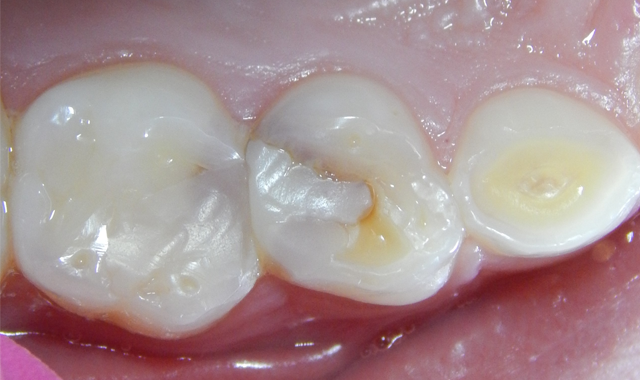

Fig. 1

A 7-year-old male patient presented with a history (maternal report) of severe dental apprehension and extensive recurrent caries. Upon examination the patient was noted to have a strong but manageable gag reflex, some airway concerns and slight “long face syndrome.” The dentition was mixed with permanent first molars and incisors. Patient reported sensitivity with eating on the upper-right quadrant and the primary molars restorations in that quadrant presented with severe micro-leakage (Fig. 1). The patient was appointed for restorative care as soon as possible.